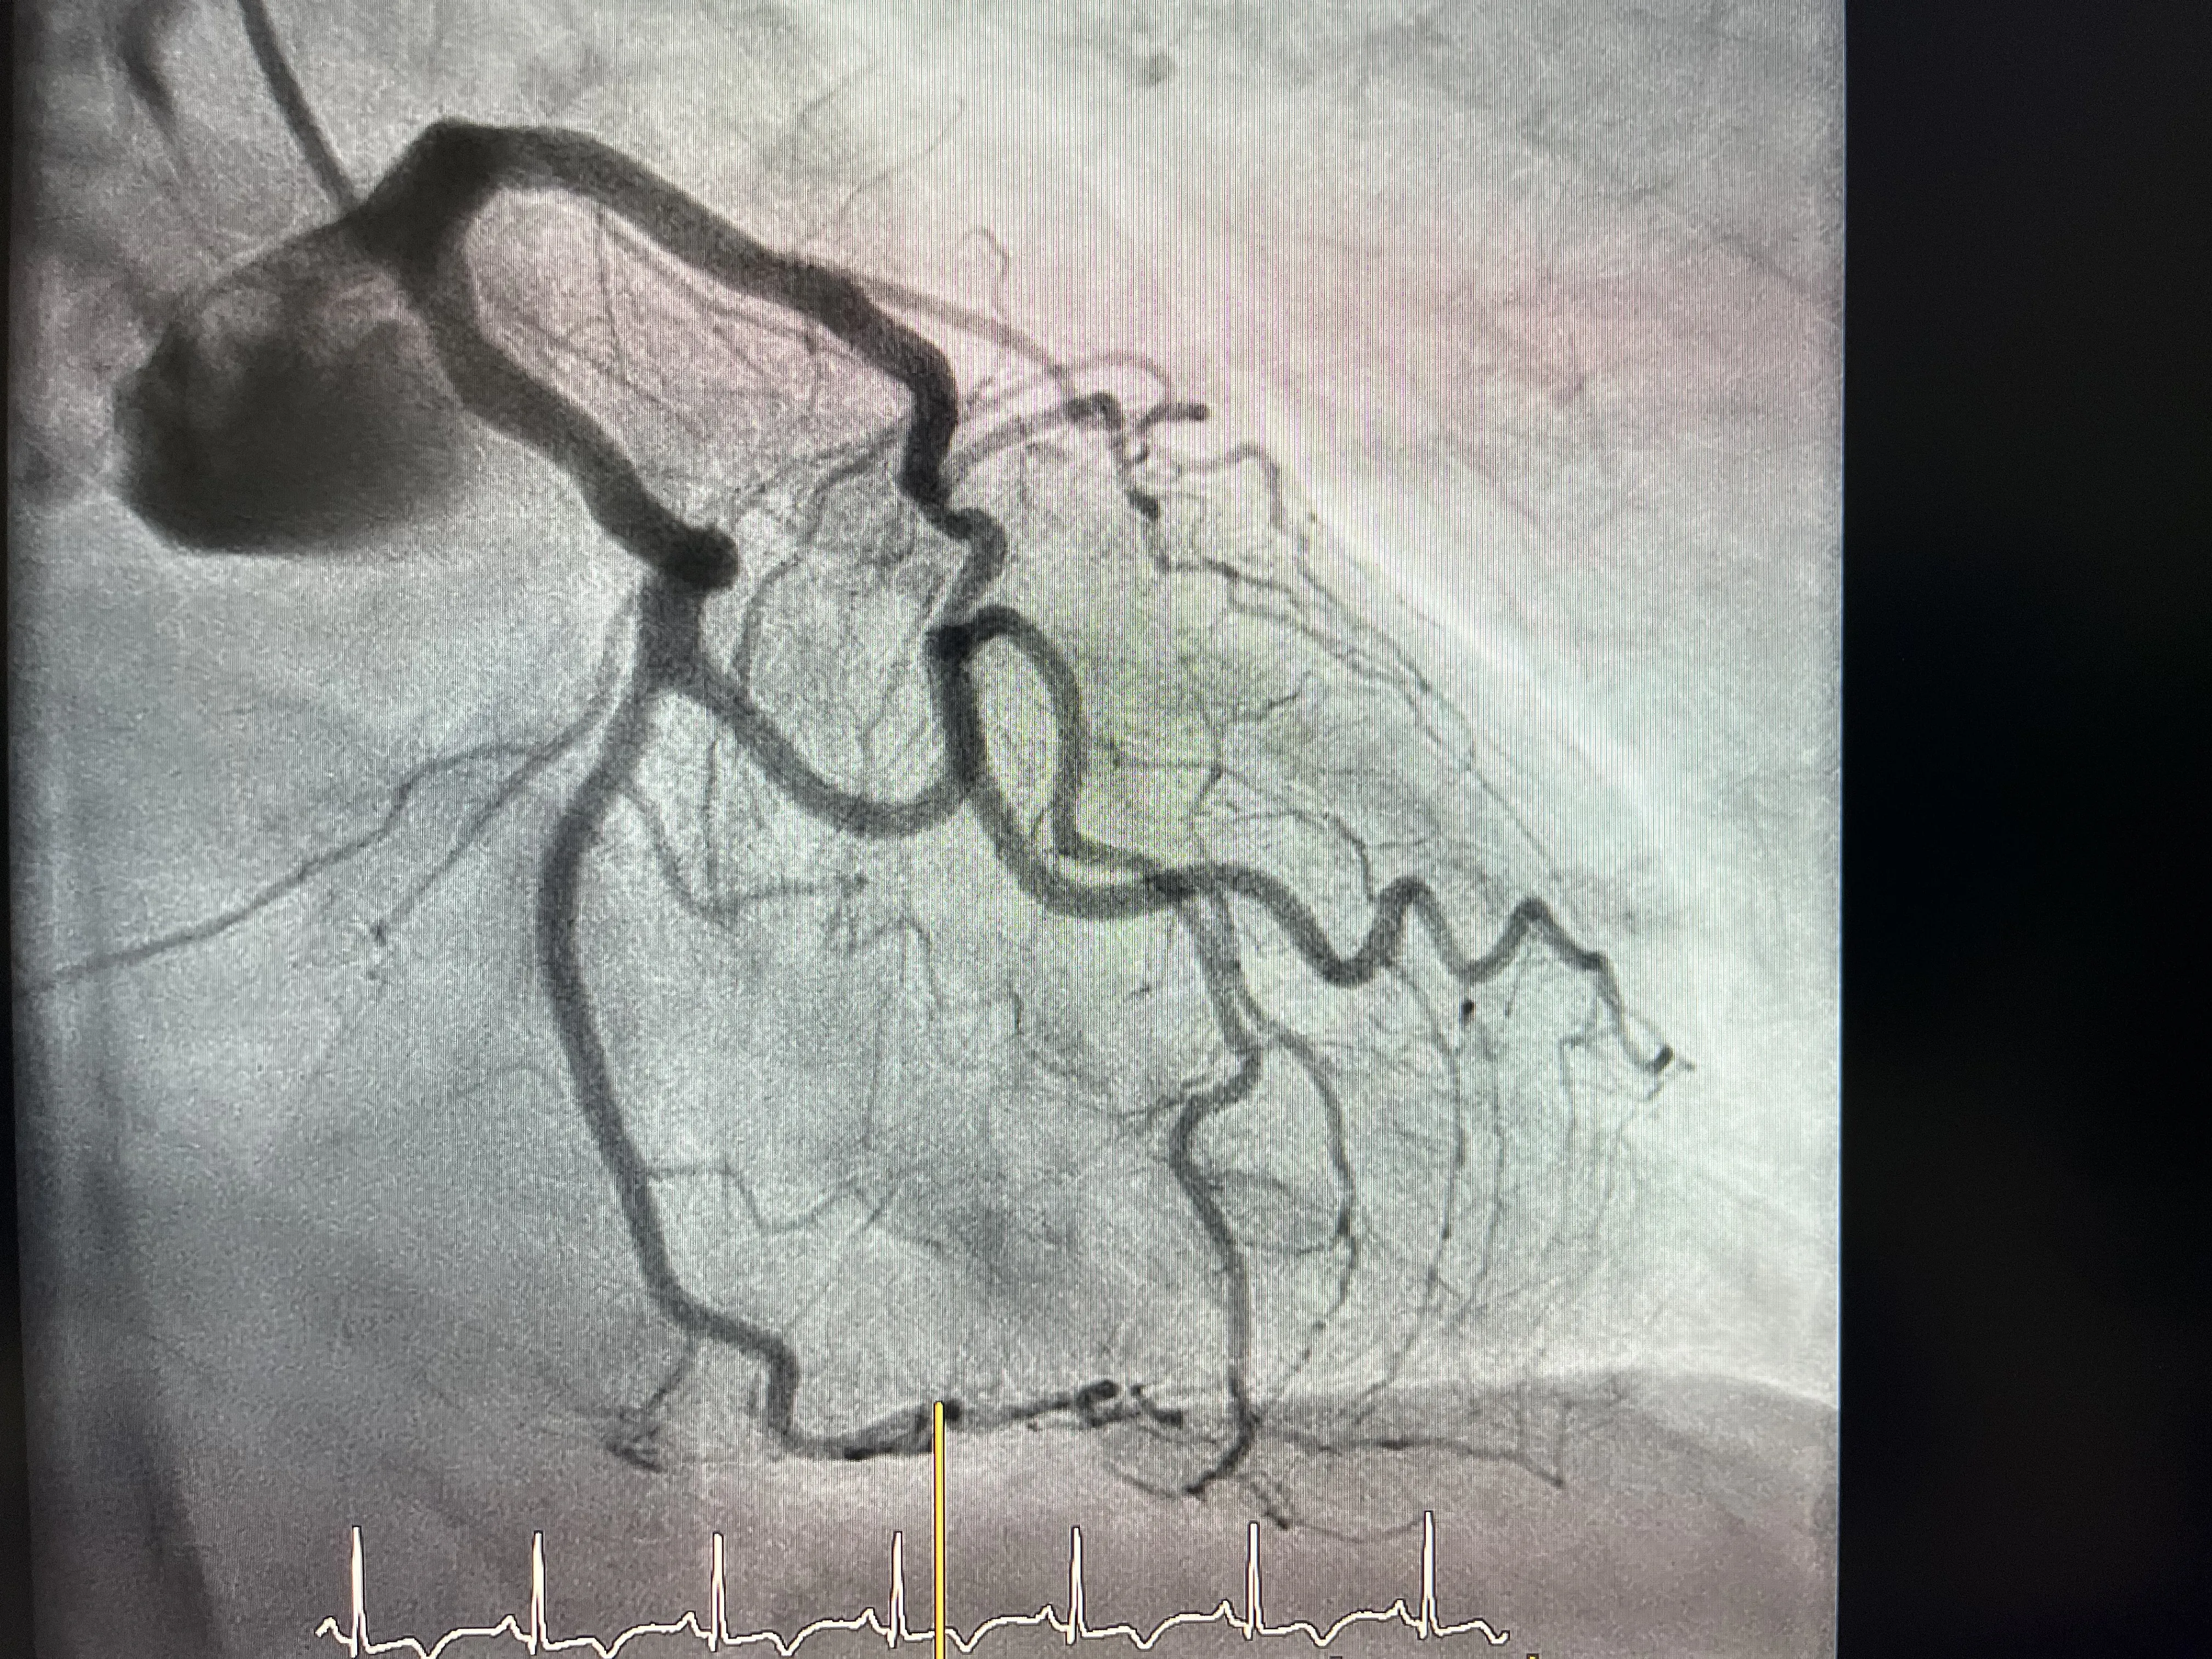

Cateterismo y hallazgo de arterias coronarias sanas

Al realizar el cateterismo en este paciente, lo que se esperaba era encontrar alguna lesión significativa que explicara el dolor y la sospecha de infarto. Sin embargo, el hallazgo fue justo el contrario: las arterias coronarias estaban sanas. La coronaria derecha no mostraba lesiones significativas y la coronaria izquierda tampoco presentaba obstrucciones que justificaran un infarto agudo. Este resultado ya marca un punto de inflexión en el razonamiento clínico.

Encontrarse con unas coronarias sin enfermedad relevante en un paciente con clínica de infarto obliga a replantear el diagnóstico. No es lo habitual en un infarto típico, donde se suele ver una arteria claramente afectada. En este caso, el cateterismo descarta la causa isquémica clásica y abre la puerta a pensar en otras entidades, entre ellas el Takobsubo. Es un momento en el que el equipo tiene que ir más allá de lo evidente y seguir investigando.

Este contraste entre una clínica muy sugestiva de infarto y unas arterias coronarias sanas es una de las claves para sospechar el Takobsubo. No basta con decir que no hay lesiones y quedarse ahí, sino que hay que buscar qué está pasando realmente en el ventrículo. Por eso, tras comprobar que ni la coronaria derecha ni la izquierda tienen lesiones significativas, el siguiente paso lógico es estudiar la función ventricular con más detalle.

El caso que presento es el de un paciente que acudió recientemente con un cuadro muy típico de infarto: dolor torácico, preocupación y una clínica que hacía pensar en un evento agudo. Siguiendo el protocolo, se decidió realizar un cateterismo para valorar las arterias coronarias y actuar con rapidez si había una obstrucción. Todo apuntaba a que se iba a encontrar una lesión significativa que explicara el cuadro, pero la realidad fue otra.

Durante el cateterismo se comprobó que la arteria coronaria derecha no tenía lesiones significativas y que la coronaria izquierda tampoco mostraba enfermedad relevante. Ante este hallazgo, el equipo médico decidió no quedarse solo con la tranquilidad de unas coronarias sanas, sino ir un paso más allá y hacer una ventriculografía. Fue en esa prueba donde se observó la hipoquinesia inferior del ventrículo izquierdo y la imagen típica de jarrón japonés asociada al Takobsubo.